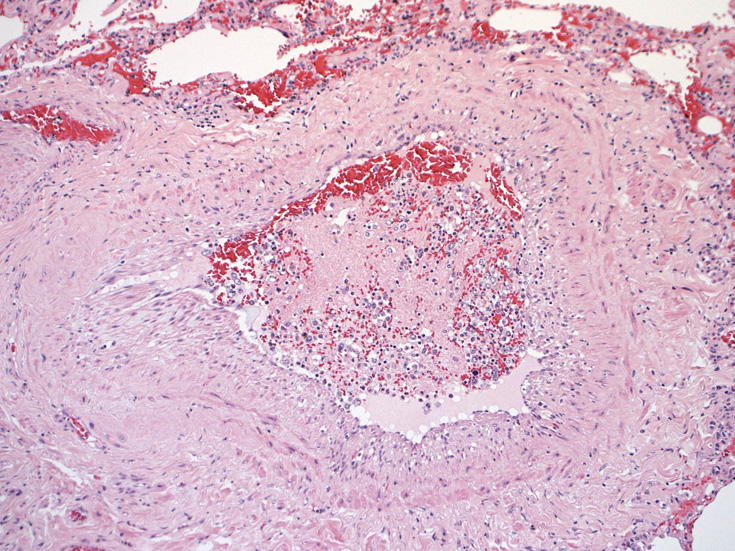

脳;くも膜下腔の小動脈内, 脳白質の細血管内に腫瘍細胞が充満している。

肺B;小気管支動脈, 肺動脈内を腫瘍細胞が閉塞する. 動脈内膜に浸潤性増殖している(B)。